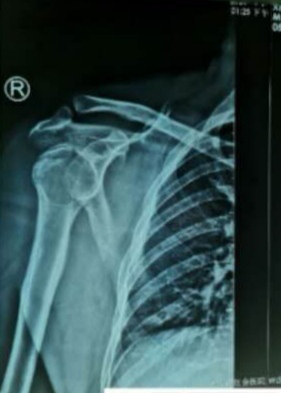

近日,一位现役军人,工作时不慎摔伤致右肩呈“方肩畸形”疼痛、活动受限,来到红会医院就诊。在得知患者身份情况后,急诊医学科手法复位室开通军人诊疗绿色通道,在急诊挂号、就诊、检查和收费等环节采取迅速便捷措施,并安排技术精湛的医生,10分钟内快速完成了肩关节复位术,得到了患者及家属的好评。